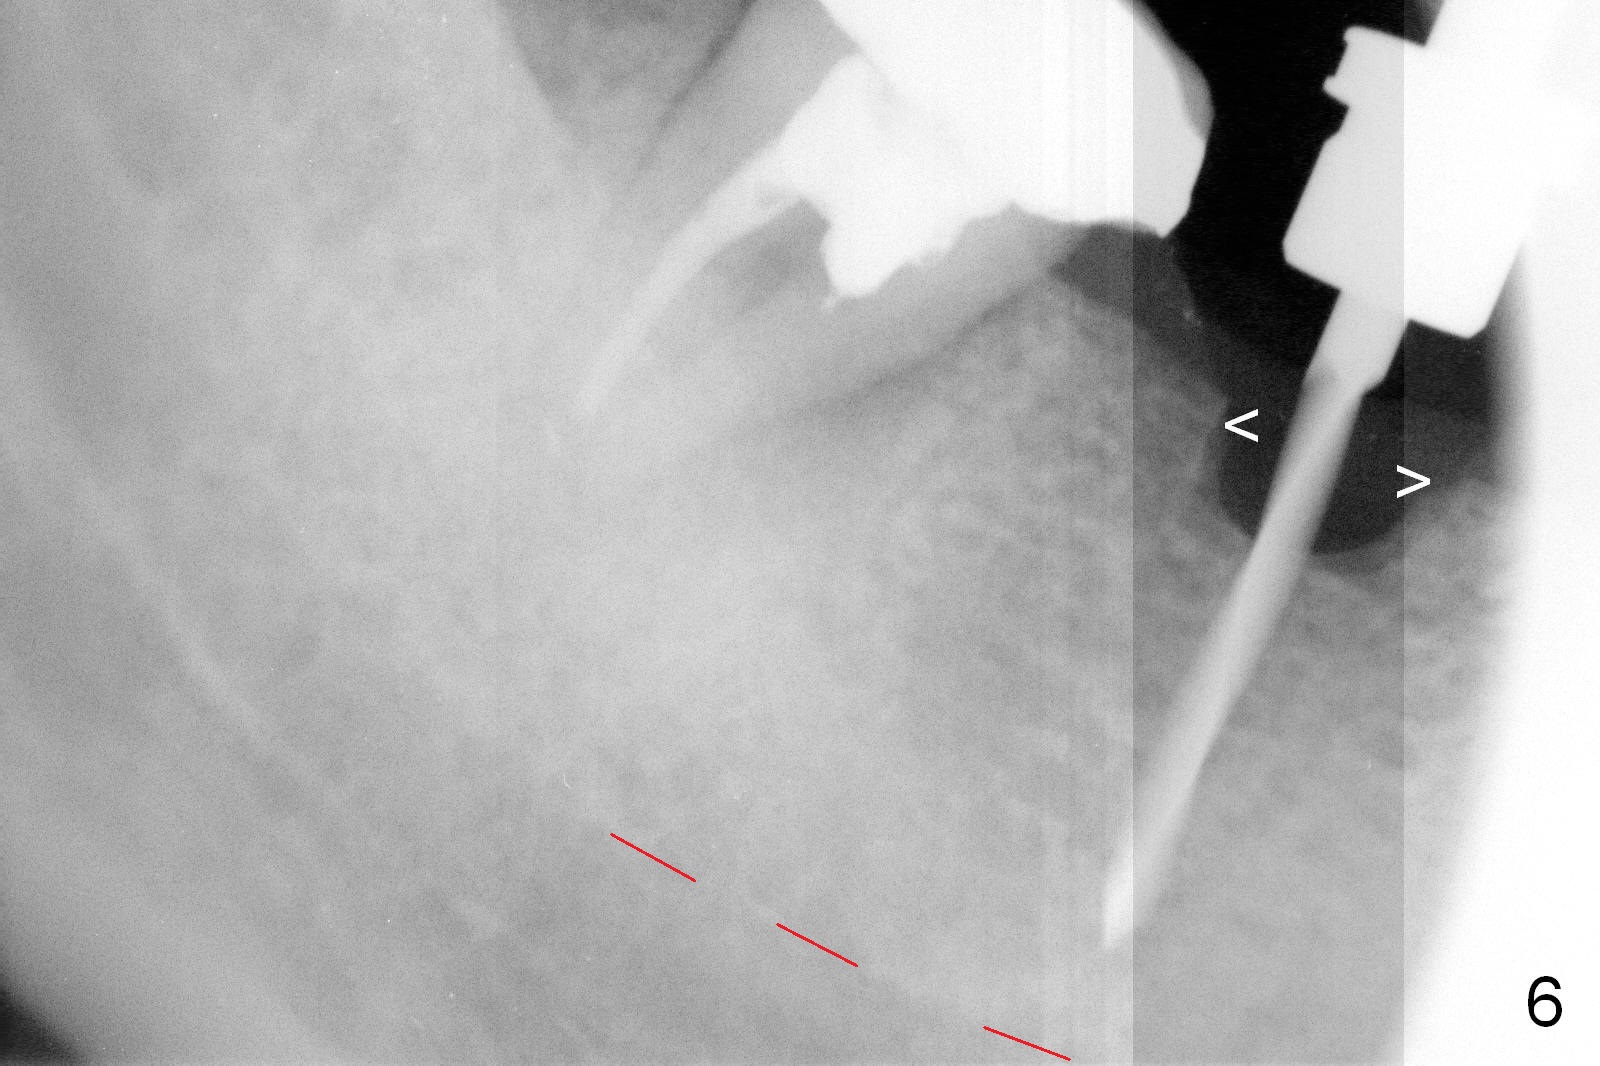

CBCT was taken (Fig.1,2 (P: pontic; S; submandibular fossa)) several months prior to #29 and 31 RCT and #31 porcelain chip (Fig.3). When the bridge is sectioned, the pointed ridge at #30 (Fig.1) is confirmed (Fig.4,5). After flattening the ridge until 6 mm buccolingually (Fig.6 arrowheads), osteotomy is initiated with 1.6 mm drill at 9 mm; there is 2.5 mm clearance from the superior border of the Inferior Alveolar Canal (red dashed line). A 4.5x9(1) mm Magicore is placed with 35 Ncm (insertion torque) after 4.3 mm Magic Drill; a 4.5 mm healing abutment (Fig.7 H). An error occurs because of using 1 mm cuff of the Magicore. Ideally 3 or 4 mm cuff should have been used because of reduction of the ridge by ~ 3 mm (Fig.2). The result of the error is failure of placing the implant at the desirable depth (<9 mm). The coronal threads are exposed and have to be covered by bone graft (autogenous bone and allograft (.5-1.5 mm) (Fig.8 *), followed by collagen dressing. Extra suturing is done to securely close the wound (Fig.9), followed by periodontal dressing (data not shown).